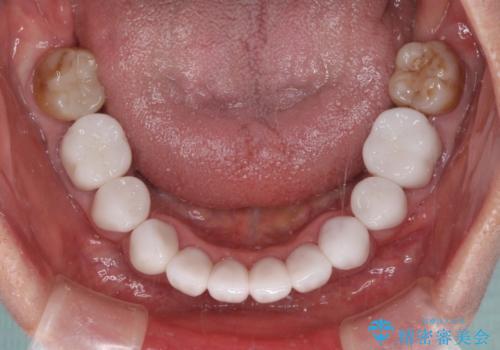

- 口元の突出感と歯の色を気にして来院された患者様です。

口元を引っ込めるために上下左右第一小臼歯4本を抜歯し、ワイヤー矯正を行うこととしました。

歯の色はホワイトニングかセラミッククラウンで対応することとしましたが、ブラックトライアングルが目立つことが予想されたため、目立つ範囲をオールセラミッククラウンで補綴することとしました。